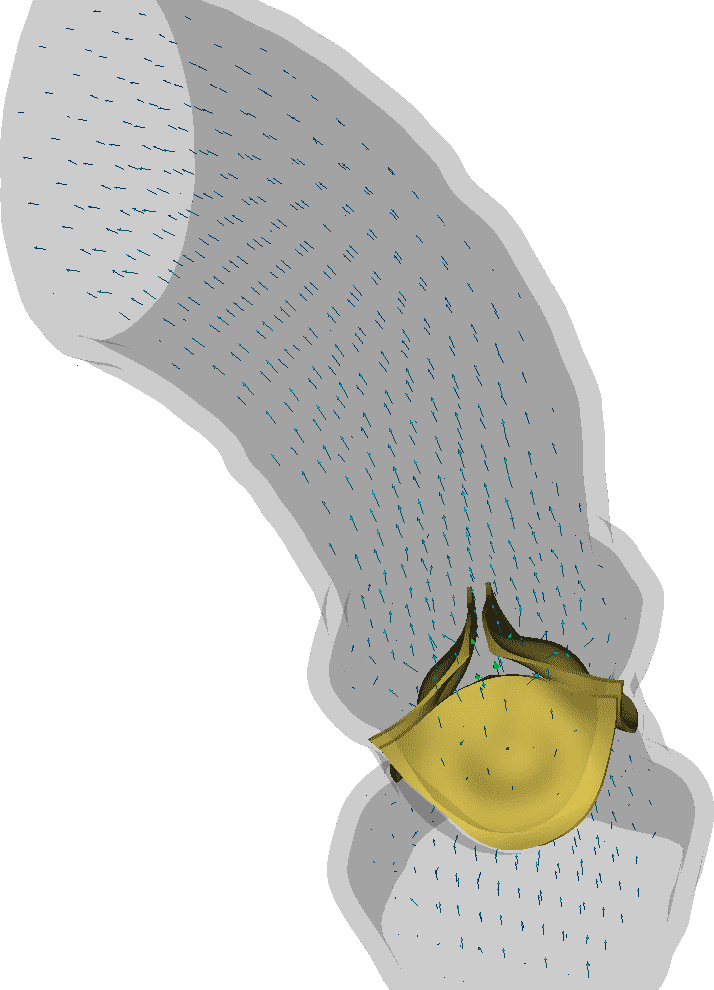

A three-dimensional representation of the aortic root and ascending aorta was generated from publicly available medical image data. This study uses one of the sample data sets from the OsiriX DICOM Image Library that consists of three-dimensional computed tomography angiography (CTA) of an anonymous patient’s chest following administration of a contrast agent. The use of a contrast agent enables better discrimination of the blood vessels and heart chambers than non-contrast CT images. The image data were acquired at the Ronald Reagan University of California at Los Angeles Medical Center in Santa Monica, CA using a Siemens SOMATOM Sensation 16 CT scanner. The image resolution is 512512355 with a voxel size of 0.470.470.5 mm. The image was processed by an anisotropic diffusion filter to mitigate noise. Sample renderings of the patient data are shown in Fig. 1.

The aortic root and ascending aorta were segmented by a semi-automated method implemented in the ITK-SNAP software. ITK-SNAP [43, 44], which is based on the Insight Segmentation and Registration Toolkit (ITK) [45, 46], provides a graphical interface for the implementation of the active contour model, also known as Kass snakes [47], for semi-automatic segmentation. The algorithm works by minimizing an energy functional that is determined by voxel intensities. The generated segmentation is shown in Fig. 2.

We first demonstrate representative results obtained using the model with fresh porcine valve leaflet parameters of Driessen et al. [38]. Specifically, we use , , and along with a fiber angle standard deviation of . In these computations, we use the coarser Cartesian grid spacing of along with a corresponding discretization of the solid model components. Fig. 6 shows leaflet kinematics and flow patterns in early systole, as the valve begins to open. Fig. 7 provides additional details of the leaflet kinematics during valve opening and closure. Fig. 8 compares the bulk hemodynamics generated by the model to the clinical data used to fit the Windkessel model. Notice that the closed valve supports a realistic pressure load during diastole without leak. There is some discrepancy between the simulated and measured aortic pressures. The aortic pressure reported from the simulation is obtained as the mean pressure along the outflow boundary , whereas the clinical pressure measurement was obtained via catheterization using a pressure probe. Because of the high Reynolds number characteristic of flow in the ascending aorta, we would expect to see relatively large differences in the pressure waveform depending on the placement of the pressure sensor. Similarly, the flow rate reported from the simulation is obtained as the net flow rate along the outflow boundary, whereas the clinical value was calculated from flow velocity measurements obtained via catheterization [41]. Because the upstream driving pressure essentially acts as a pressure source in our model, we do not expect to obtain identical flow rates. (Notice, for instance, that fluctuations in the clinical data indicate nontrivial forward flow during diastole.) Nonetheless, the pressures and flow rates generated by the model are in generally good agreement with the corresponding clinical values. Stroke volume in the simulation is , which is somewhat lower than the clinical stroke volume of but still in the physiological range.